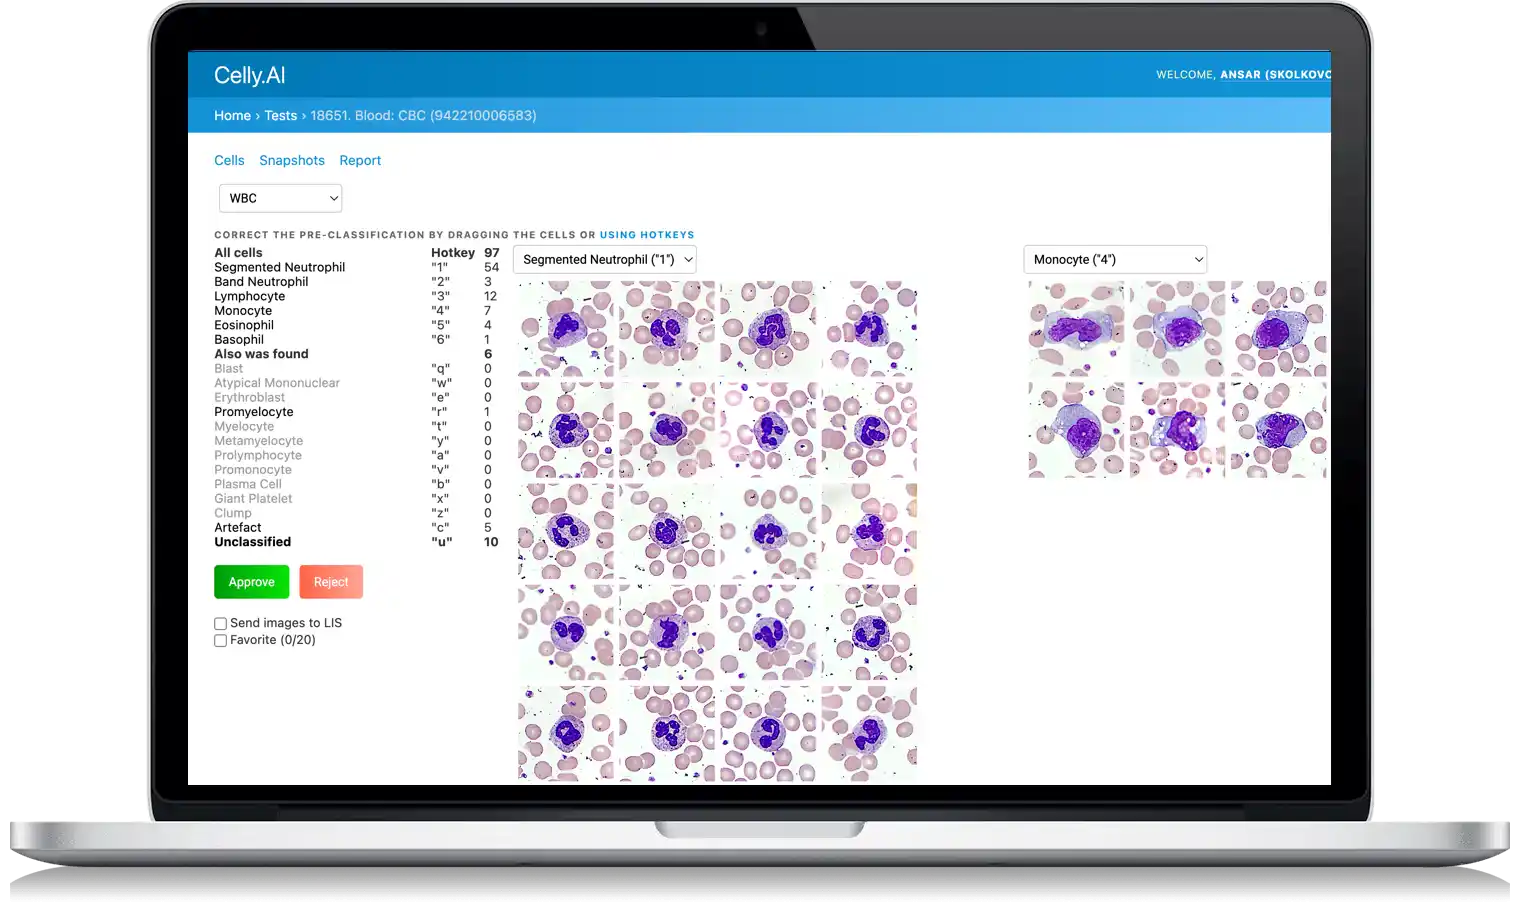

Hematology

Precise automated WBC differential counts with advanced morphology recognition in blood and bone marrow smears

State-of-the-art computer vision and machine learning algorithms that transform laboratory diagnostics

Lightning-Fast Analysis

Celly's advanced AI algorithms identify cell patterns and abnormalities in seconds, transforming hours of manual work into minutes of automated precision.